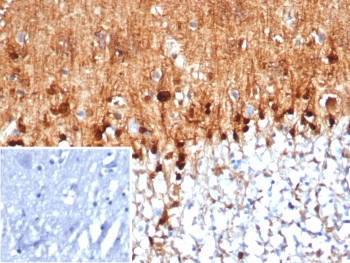

Immunohistochemistry analysis of S100B / Astrocyte Marker antibody (clone S100B/4159) in human brain tissue. FFPE human brain demonstrates strong cytoplasmic and nuclear HRP-DAB brown staining in astrocyte-like cells distributed throughout the parenchyma, consistent with S100B expression. Staining highlights cells with branching morphology characteristic of astroglial cells, while neuronal cell bodies show comparatively weaker signal. Nuclei are counterstained blue. The inset image represents a secondary antibody negative control in which PBS was used in place of the primary antibody and shows absence of specific staining.